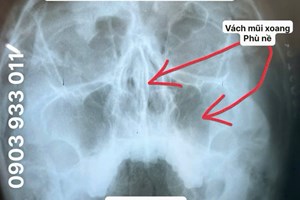

Sau khi thăm khám và kiểm tra chuyên khoa, bác sĩ chẩn đoán chị bị viêm xoang hàm cấp kèm ứ nhiều dịch ở xoang hàm trái. Theo chuyên môn, khi niêm mạc xoang bị viêm, lỗ thông xoang có thể bị bít tắc khiến dịch viêm không thoát ra ngoài, dẫn đến tình trạng ứ đọng. Điều này gây đau nhức vùng mũi, hốc mắt, nhức đầu và tăng tiết dịch mũi họng.